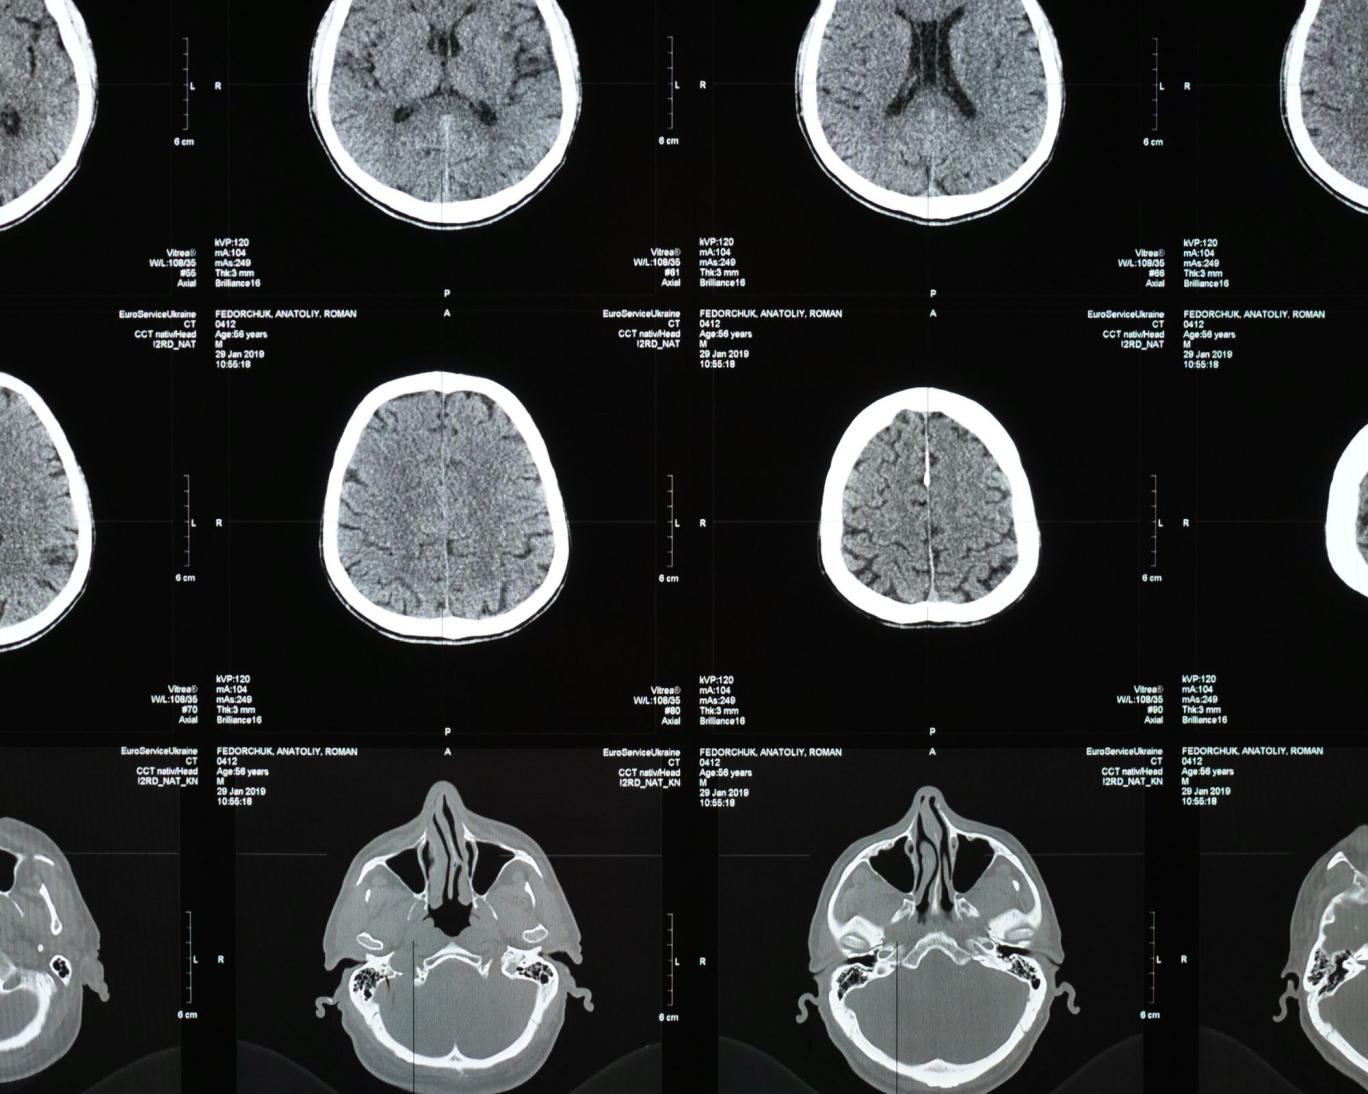

بیمار در اواخر ژانویه ۲۰۲۱ در بیمارستان بستری شد و سپس اسکنهای مغزی نشان داد که یک ضایعه در مغز او وجود دارد. پس از آن در ژوئن ۲۰۲۲ در اتاق عمل مشخص شد که وجود یک کرم زنده سبب نشانههای بیماری این زن بوده است.